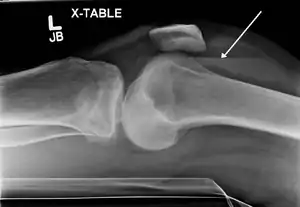

![]() Ліпогемартроз (скопичення крові та жиру в порожнині суглоба) в результаті перелому в області міжвиросткового підвищення великої гомілкової кістки. Стрікою позначений рівень рідини між жиром, що розміщається над кров'ю. Ліпогемартроз (скопичення крові та жиру в порожнині суглоба) в результаті перелому в області міжвиросткового підвищення великої гомілкової кістки. Стрікою позначений рівень рідини між жиром, що розміщається над кров'ю. | |